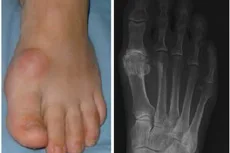

The extent of joint damage can also vary among individuals with hallux rigidus. In some cases, the cartilage within the MTPJ may show early signs of wear and tear, with minor irregularities and roughening of the joint surfaces. In more advanced stages, the cartilage may become severely eroded, leading to the formation of bony spurs (osteophytes) and deformity of the joint. These bony spurs can cause pain and discomfort, particularly when they rub against surrounding soft tissues or press against tight-fitting shoes.

In the context of hallux rigidus, particular attention is drawn to key structures around the great toe metatarsophalangeal joint (MTPJ). The first metatarsal bone and proximal phalanx (phalanges) interact at this joint, crucial for maintaining alignment and enabling movement.

Cartilage within the MTPJ ensures smooth movement, but in big toe arthritis, cartilage deterioration leads to inflammation and stiffness.